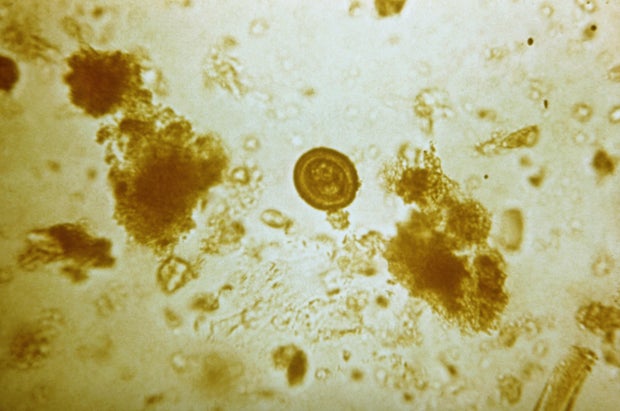

Класс Cestoda (ленточные черви, или цестоды) - КиберПедия

Сколекс бычьего цепня. Гермафродитный членик бычьего цепня.